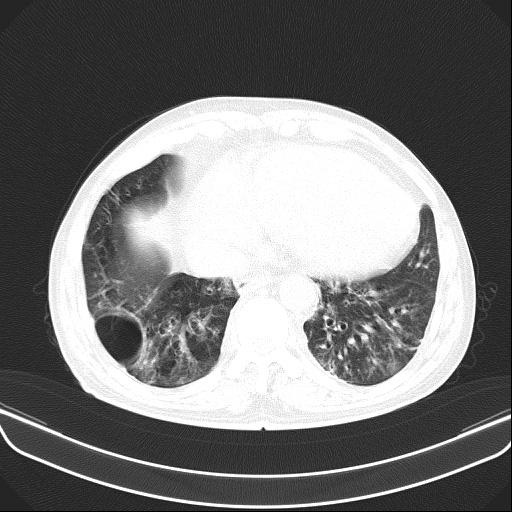

6月11日,会昌县人民医院呼吸内科接诊一呼吸衰竭的患者胡某,男性,54岁,主诉反复咳嗽、咳痰、气促10余年加重伴下肢浮肿10天入院。呼吸内科医生对胡某进行仔细查体:患者口唇及颜面、四肢紫绀明显,颈静脉怒张,桶状胸,肋间隙增宽,叩诊过清音,双肺呼吸音减弱,可闻及较多干湿性啰音,腹膨隆,肠鸣音减弱,双下肢重度浮肿。结合各类辅助检查,确诊胡某为“慢性阻塞性肺疾病、慢性呼吸衰竭、慢性肺源性心脏病失代偿期、重度肺动脉高压”。

不吸氧情况下胡某SPO2:67%,吸氧3L/min情况下SPO2:82%,治疗难度大,如何纠正严重的呼吸衰竭是重点。胡某重度浮肿、尿量少、腹胀明显、进食少,病情危重,随时有可能出现昏迷。同时,胡某神志清楚,无法配合无创双水平呼吸机辅助通气,不纠正呼吸衰竭,抗感染、祛痰、平喘、强心、利尿、扩血管等常规治疗几乎无效。

按照常规,医生会建议患者转ICU气管插管接有创呼吸机辅助通气或者转上级医院救治,但胡某拒绝转ICU,拒绝转上级医院,不接受气管插管及面罩式无创呼吸机辅助通气。经科内医生组讨论后决定:为避免患者气管插管或切开,使用经鼻高流量氧疗治疗,同时配合抗感染,雾化解痉祛痰,甲泼尼龙、多索茶碱平喘,托拉塞米、螺内酯利尿等治疗。经过13天时间治疗,胡某症状缓解、浮肿消退,好转出院。